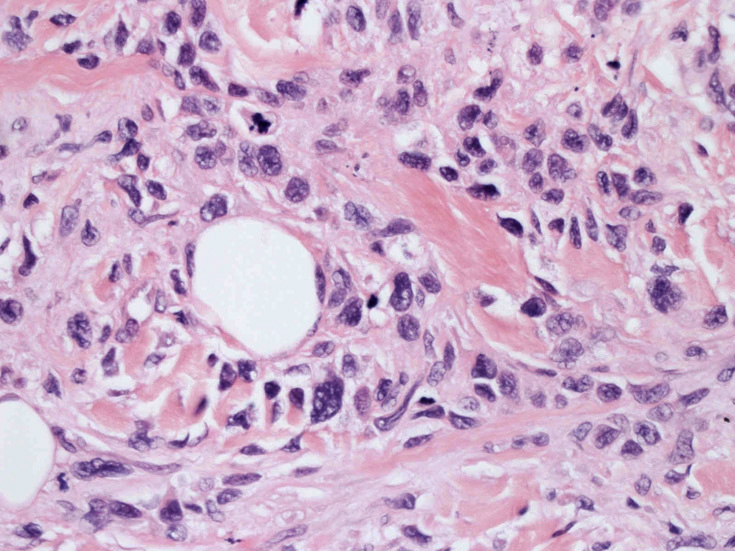

皮膚に異型細胞の浸潤がみられる。異型細胞は表皮内に浸潤するほか、表皮真皮境界部, 真皮, 皮下脂肪組織にもびまん, 結節様の浸潤所見を示す。血管周囲に浸潤、集蔟する所見も多く見られる。 増殖浸潤細胞の核には類円形や腎臓形, またはへこみ, 切れ込み, 溝などを有する多型な核が認められる。クロマチンは粗でvesicularな核が多い。核小体の明らかな核もある。好エオジン性の核内封入体様構造も少数に見られた。mitosisは容易に認められる。hyperchromaticな多型核, bizzarreな細胞が高頻度に認められ異型度は高いと考えられる。細胞質は境界不明瞭, 淡明または泡沫様の 好エオジン性胞体である。

免疫染色 浸潤細胞はCD1a+, S100+, Langerin+, HLA-DR+, CD4+, CD45+, CD68+. MIB-1 index:24.4%

Speaker's Pathological Diagnosis: Langerhans cell sarcoma, skin, rt. knee, biopsy